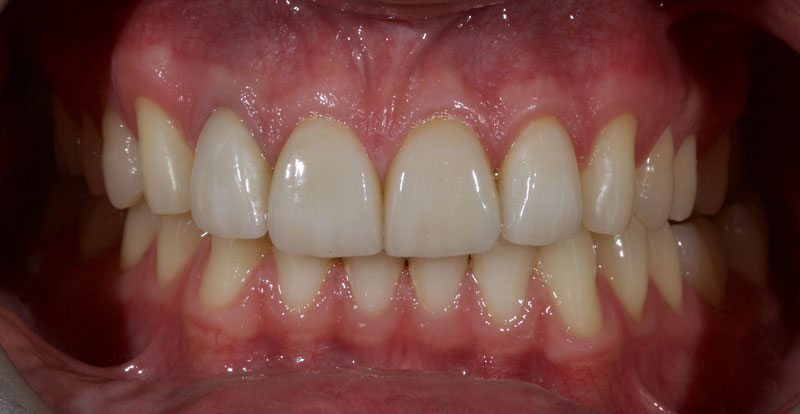

Treatment with direct resin is challenging due to the multiple diastemata and the potential risks of overhangs, defective contact points, and canted midlines. See Fig. 1 (before treatment) and Fig. 2 (after treatment).